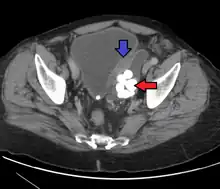

Diverticulum of the urinary bladder of a 59-year-old man, transverse plane